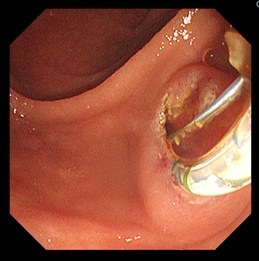

2胆管の出口(十二指腸乳頭部)に対して切開あるいはバルーン拡張を行い出口を広げます。(写真B)

![]() 写真B |